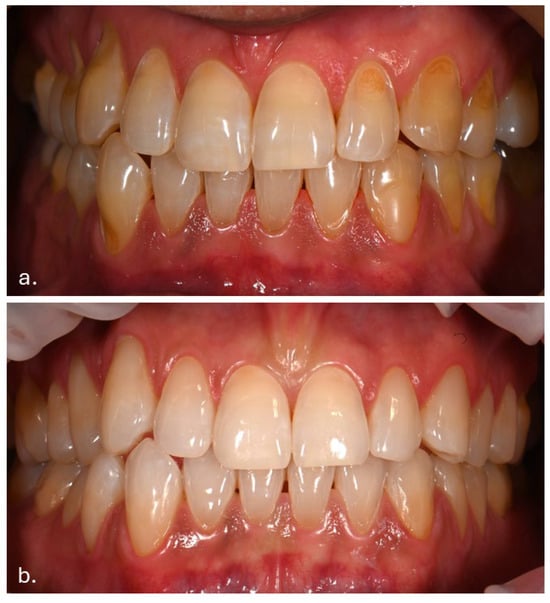

Three months after cessation of Melanotan II therapy, gingival pigmentation had diminished but was not completely resolved (Figure 6).

Figure 6.

Marked reduction in brown pigmentation, although the mucosal appearance had not completely reverted to its pre-Melanotan II condition.

The buccal mucosa demonstrated marked improvement compared with its appearance during active therapy (Figure 7).

Figure 7.

Clinical appearance of the buccal mucosa three months following discontinuation of Melanotan II therapy.